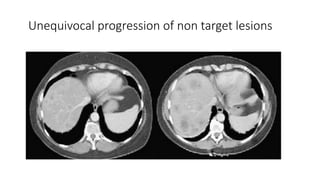

Clarification of Unequivocal

Progression of Nontarget Lesions

• When measurable disease or a target lesion is present, to call it as

progression based on nontarget lesion there should be substantial

worsening in nontarget disease, which leads to an increase of overall

tumor burden even with SD or PR in target disease

• such that, even in presence of SD or PR in target disease, the overall

tumour burden has increased sufficiently to merit discontinuation of

therapy

• Modest increase in the size of one or more nontarget lesions is usually

not sufficient.

Unequivocal progression of non target lesions